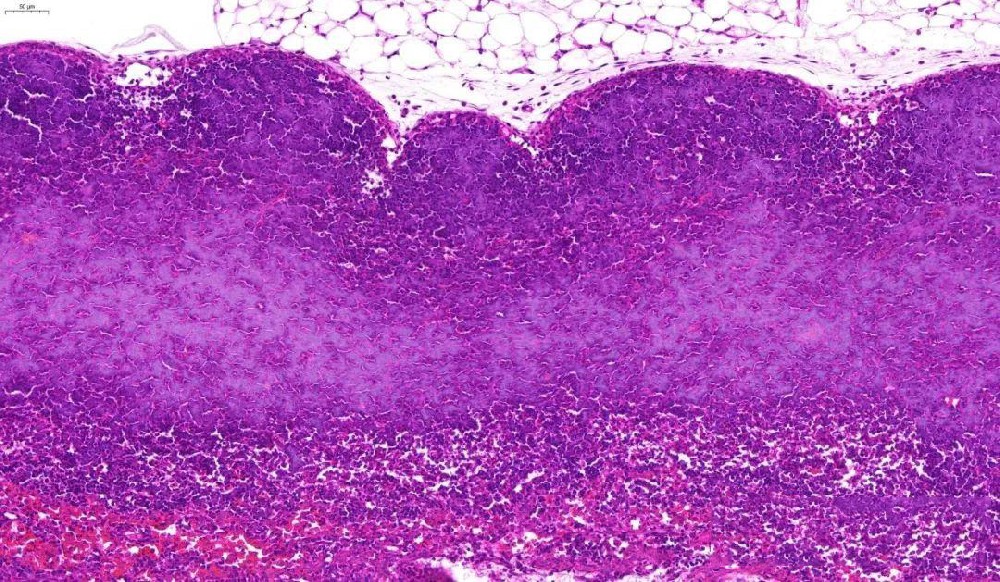

(一)實驗目的通過蘇木素(堿性染料)和伊紅(酸性染料)對組織切片進行染色,使細胞核、細胞質(zhì)呈現(xiàn)不同顏色,清晰顯示組織細胞的形態(tài)結(jié)構(gòu)、排列方式,為病理診斷提供基礎依據(jù)。(二)實驗材料1. 樣本:已烤好的病理···